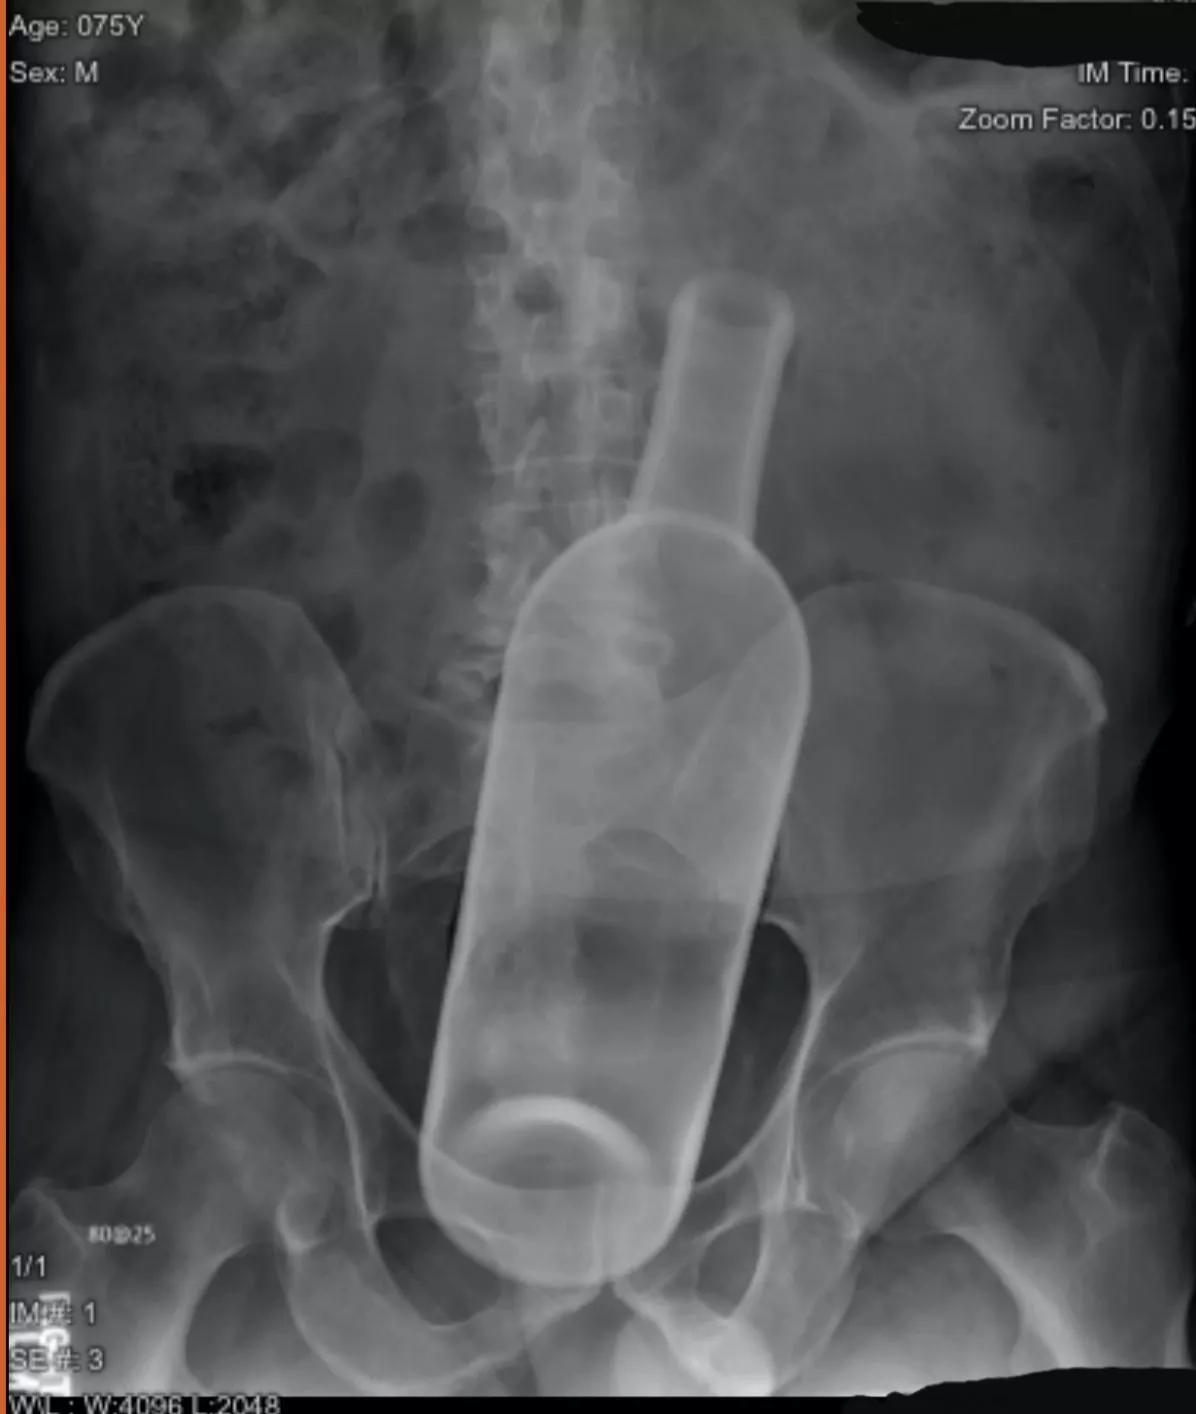

In response to the other post involving a wine bottle and Cindy rose

In response to the other post involving a wine bottle and Cindy rose posted by drifteddreams Previous Next